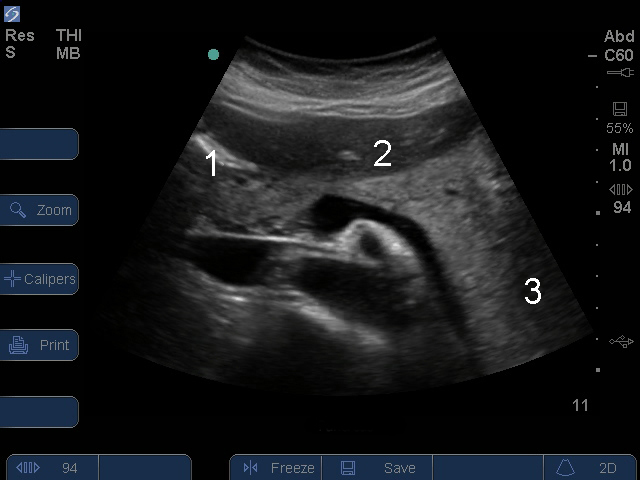

膵臓横断面

頭部

身体

後部